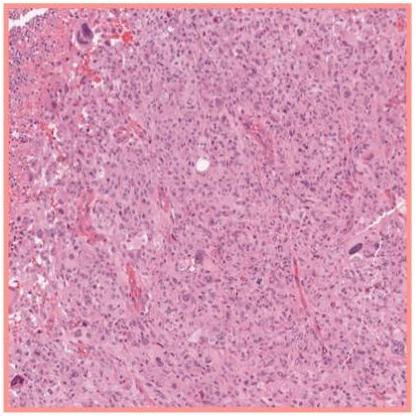

The introduction of this research paper highlights the transformative advancements in computational pathology, driven by the integration of digital slide scanning, artificial intelligence (AI), large datasets, and high-performance computing resources. Researchers have successfully applied deep learning techniques to various tasks such as cancer subtyping, grading, metastasis detection, and treatment response prediction. Despite these advancements, the role of natural language in pathology remains underutilized, which could enhance model development and facilitate user interaction with AI systems.

The paper emphasizes the potential of multimodal large language models (MLLMs) and generative AI to revolutionize computational pathology by incorporating natural language processing. While existing models have shown promise in diagnostic tasks, they currently lack the capability to serve as interactive companions for pathologists. The authors propose that an AI copilot could significantly aid clinical decision-making, education, and research by providing initial assessments of histopathology images, suggesting differential diagnoses, and summarizing morphological features of large datasets. This innovative approach could democratize access to expert guidance in pathology, addressing disparities in healthcare provision.

In this section, the authors discuss the development and evaluation of PathChat, a multimodal generative AI copilot designed for human pathology. PathChat integrates a custom, fine-tuned multimodal large language model (MLLM) that combines a vision encoder pretrained on extensive histology image data with a 13 billion parameter Llama 2 language model. This architecture allows PathChat to process and respond to complex pathology-related queries by leveraging both visual and textual inputs. The model was evaluated against state-of-the-art competitors, including LLaVA and GPT-4Vision, demonstrating superior diagnostic accuracy and response quality in both multiple-choice and open-ended question formats.

The evaluation results indicate that PathChat significantly outperforms the other models, achieving an accuracy of 78.1% in image-only settings and 89.5% when additional clinical context is provided. In open-ended question answering, PathChat scored an overall accuracy of 78.7%, surpassing GPT-4Vision by 26.4%. The authors highlight that PathChat excels particularly in tasks requiring detailed morphological analysis of histology images, while it performs comparably to GPT-4Vision in clinical knowledge retrieval tasks. The findings suggest that PathChat has the potential to enhance pathology education, research, and clinical decision-making, particularly in complex diagnostic scenarios. Future improvements may focus on refining the model’s ability to handle diverse input formats and ensuring accurate identification of invalid queries.